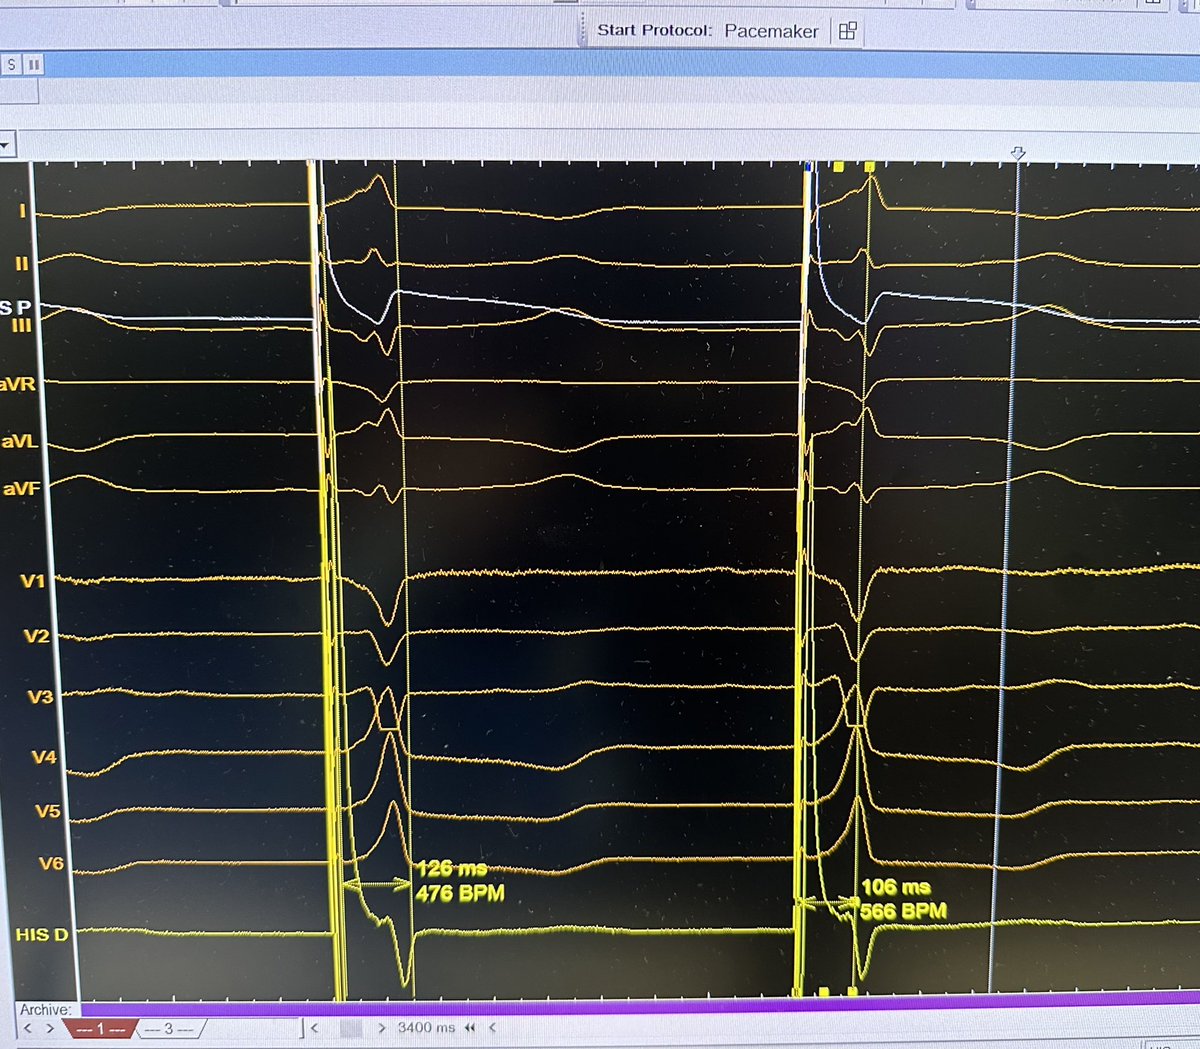

Planning to implant an AVEIR AR in a pt with previous chemotherapy,renal insufficiency,repeated syncope,sinus bradycardia,and CS massage with prolonged sinus arrest.We tested the AV node response to CSM with atrial pacing;this was the response.Finally,we implanted a DDD with LBBP